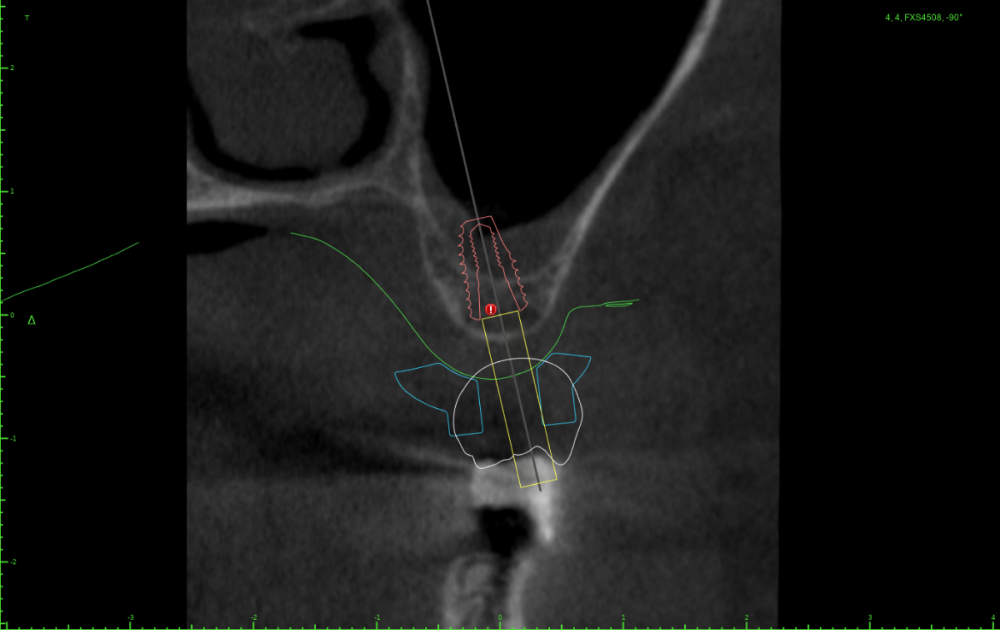

Женька Опубликовано 24 июля, 2023 Поделиться Опубликовано 24 июля, 2023 Тема ради одной фотки конечно, но всё-таки вопрос есть. Говорят МСТ профайлер не задевает стенки имплантата. Кмк, всё-таки задевает. Или всё-таки кажется? По кейсу: 2 имплантата, оба по шаблону. Черт дёрнул пройти глубже чем планировал в 1.6, фрезой перфо не создал, но кортикалку в ноль убрал. И при отслойке всё-таки порвал немного. Тампонировал губками, пробы отрицательные. Вроде нигде не перемудрил в этот раз, @АнтонТЛТ ? 3 Ссылка на комментарий

Женька Опубликовано 25 июля, 2023 Автор Поделиться Опубликовано 25 июля, 2023 23 часа назад, Женька сказал: Но буду честен, можно было чутка 1.4 наклонить и сооснопоставить. я же уже говорил об этом. Вот если бы параллелил по 1.6 . Как по мне так себе позиция Поэтому выбрана такая И соответственно если бы параллелил по 1.4 Ссылка на комментарий

АнтонТЛТ Опубликовано 25 июля, 2023 Поделиться Опубликовано 25 июля, 2023 А сагиттальный срез? Ссылка на комментарий

АнтонТЛТ Опубликовано 25 июля, 2023 Поделиться Опубликовано 25 июля, 2023 По фото выглядит так как будто установлены так Ссылка на комментарий

Женька Опубликовано 26 июля, 2023 Автор Поделиться Опубликовано 26 июля, 2023 (изменено) @АнтонТЛТ , не, не делали. Через полгодика сделаю, как раз пластика с другой стороны (сетка, которую выкладывал) должна созреть.) Возможно из-за синуса ось сместилась ну и были определённые проблемы привязки КТ и скана. Зубы есть, но программа не хотела даже по точкам сопоставлять. Пришлось в ручную. саггиталь не могу выстроить как не кручу, чтобы оба болта попали. Изменено 26 июля, 2023 пользователем Женька Ссылка на комментарий